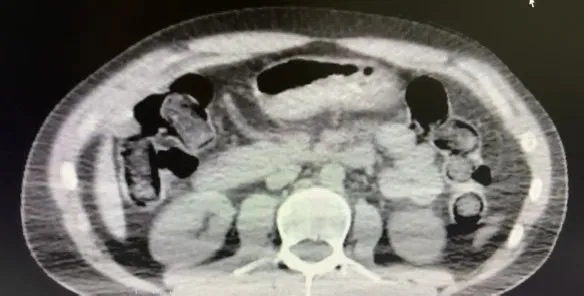

Şahısların konutlarında ve kullandıkları araçlarda yapılan aramalarda; 101 kapsül halinde toplam 722 gram metamfetamin maddesi, 1 adet hassas terazi, uyuşturucu sevkiyatında kullanılan çeşitli materyaller ile uyuşturucu ticaretinden elde edildiği değerlendirilen 20 bin 210 TL, 1.320 Euro ve 10 ABD Doları ele geçirildi.